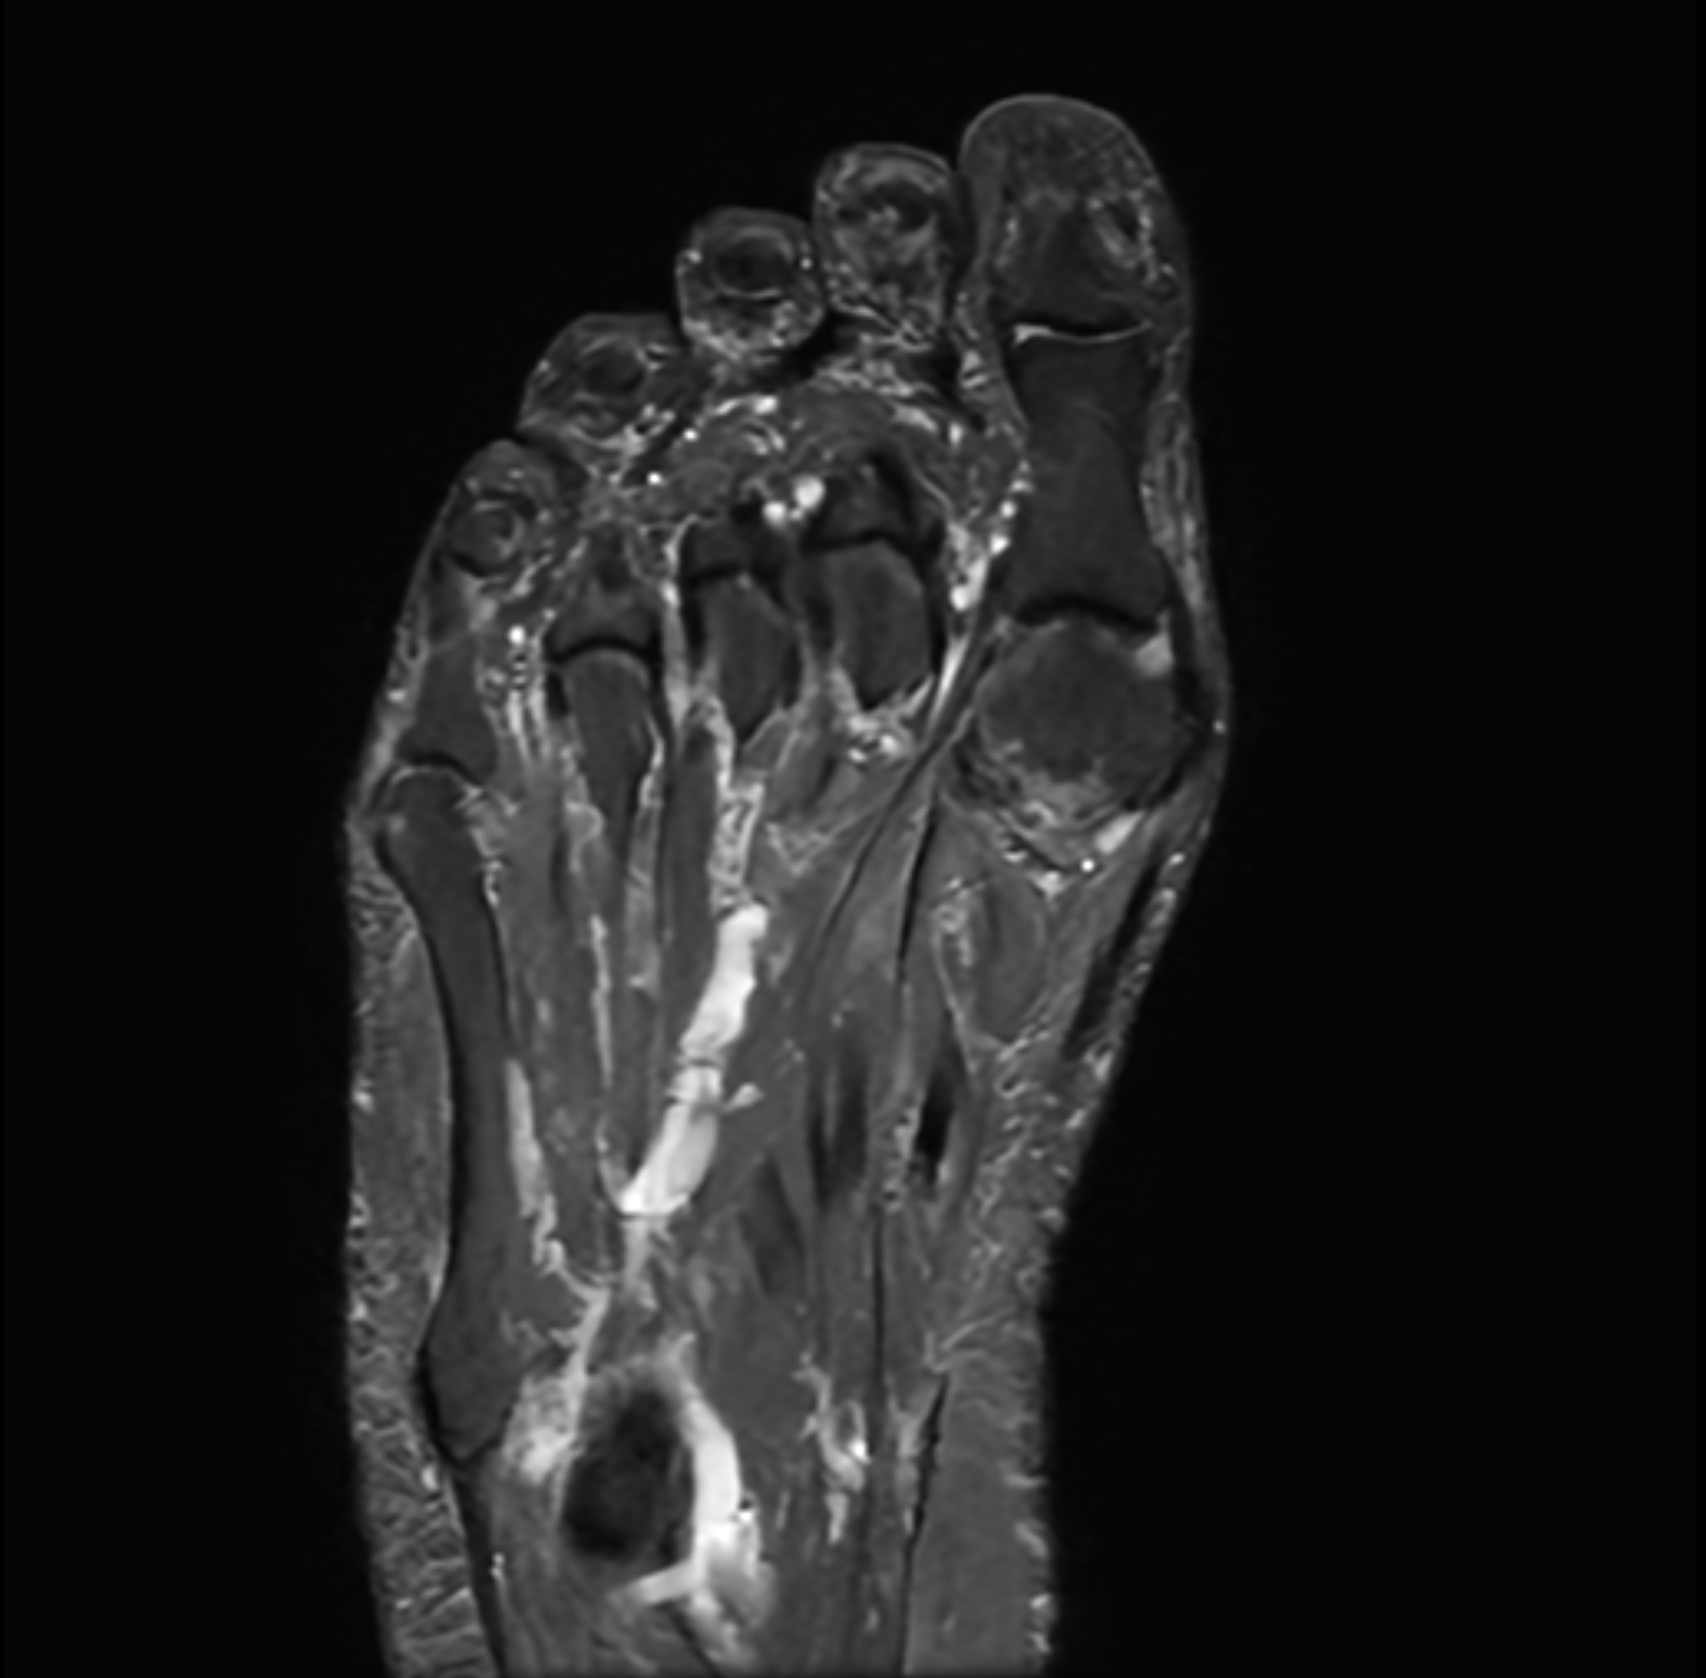

Med en magnetkameraundersökning (MR) av foten får du en högupplöst bild av fotens inre strukturer – inklusive skelett, ledbrosk, senor, ligament, ledkapslar och mjukdelar. Undersökningen är helt utan strålning och ger överlägsen detaljnivå jämfört med vanlig röntgen eller ultraljud, särskilt vid komplexa smärt- eller belastningsrelaterade problem i fot och häl.

MR fot är särskilt användbar vid långvarig eller svårförklarad fotsmärta, misstänkta stressfrakturer, senskador, artros, nervinklämning eller inflammation. Undersökningen är smärtfri, tar cirka 30 minuter, din remiss skickas iväg direkt efter genomgång tillsammans med en av våra läkare och du får sedan en kallelse för magnetröntgen hos en av radiologienheterna. Smärta, stelhet eller svullnad i foten kan bero på många olika tillstånd – från överbelastning och mikrofrakturer till reumatiska ledsjukdomar eller mjukdelstumörer.

MR ger en mycket tydlig bild av både benstruktur och mjukdelar, vilket gör undersökningen särskilt värdefull för att säkerställa diagnos inför behandling eller eventuell kirurgi.